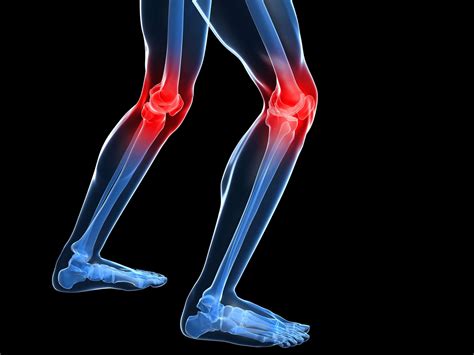

Symptoms of Artritis en la Rodilla

The symptoms of artritis en la rodilla can vary depending on the type and severity of the condition. Common symptoms include:

• Pain: Persistent pain in the knee joint, which can worsen with activity and improve with rest.

• Swelling: Inflammation and swelling around the knee joint.

• Reduced Range of Motion: Difficulty bending or straightening the knee fully.

• Instability: A feeling of the knee giving way or buckling.